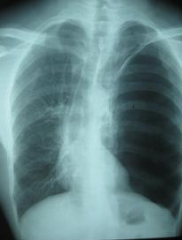

肺气肿